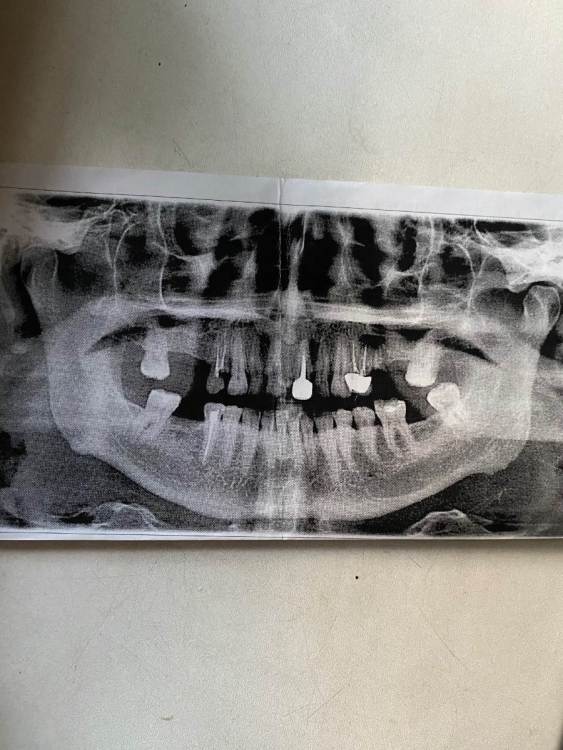

Bonya Опубликовано 26 сентября, 2023 Поделиться Опубликовано 26 сентября, 2023 Уважаемые доктора, прошу совета: какие импланты поставить на обе челюсти? Надо будет еще что-то удалять? Можно ли обойтись без синус лифтинга с установкой импланта какой марки? Ссылка на комментарий

Irouil Опубликовано 26 сентября, 2023 Поделиться Опубликовано 26 сентября, 2023 Под вопросом два 4-х зуба на верхней челюсти, надо осматривать в полости рта, возможно проводить диагностическую препаровку и решать их судьбу Вероятнее всего потребуется установить по 2 импланта на сторону, слева более вероятен синус-лифт, справа - менее, надо смотреть КЛКТ На нижней челюсти вероятнее всего просто по одному импланту на сторону Ссылка на комментарий